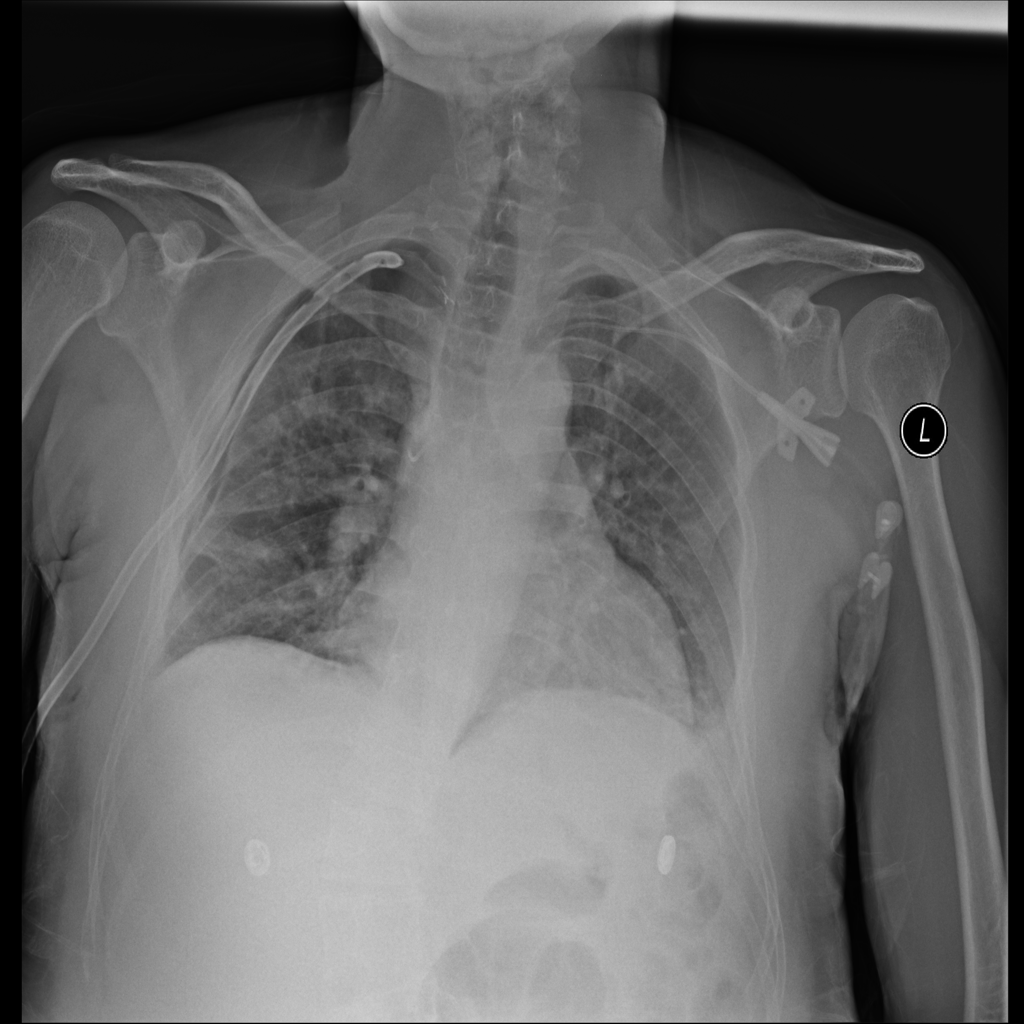

Pneumothorax

Pneumothorax means air is present outside the lung in the pleural space, which can allow part of the lung to collapse. It is an important imaging finding because the size and clinical impact can vary widely.

Showing up to 90 reference images for Pneumothorax.